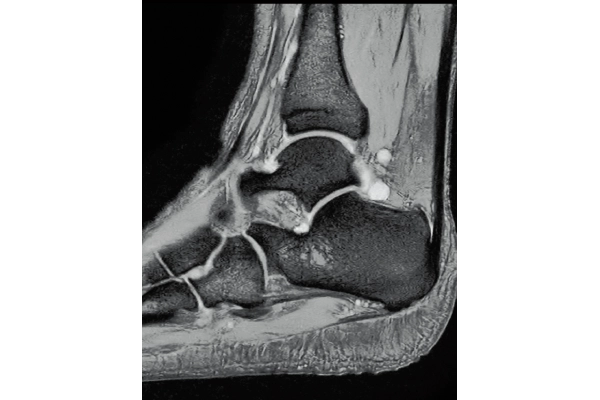

T2*WI Multi Echo,

0.38×0.38×2.0mm

0.35×0.40×3.0mm, 2:55

3D Bone

0.93×0.93×1.2(0.6)mm

1.1×1.1×1.2(0.6)mm